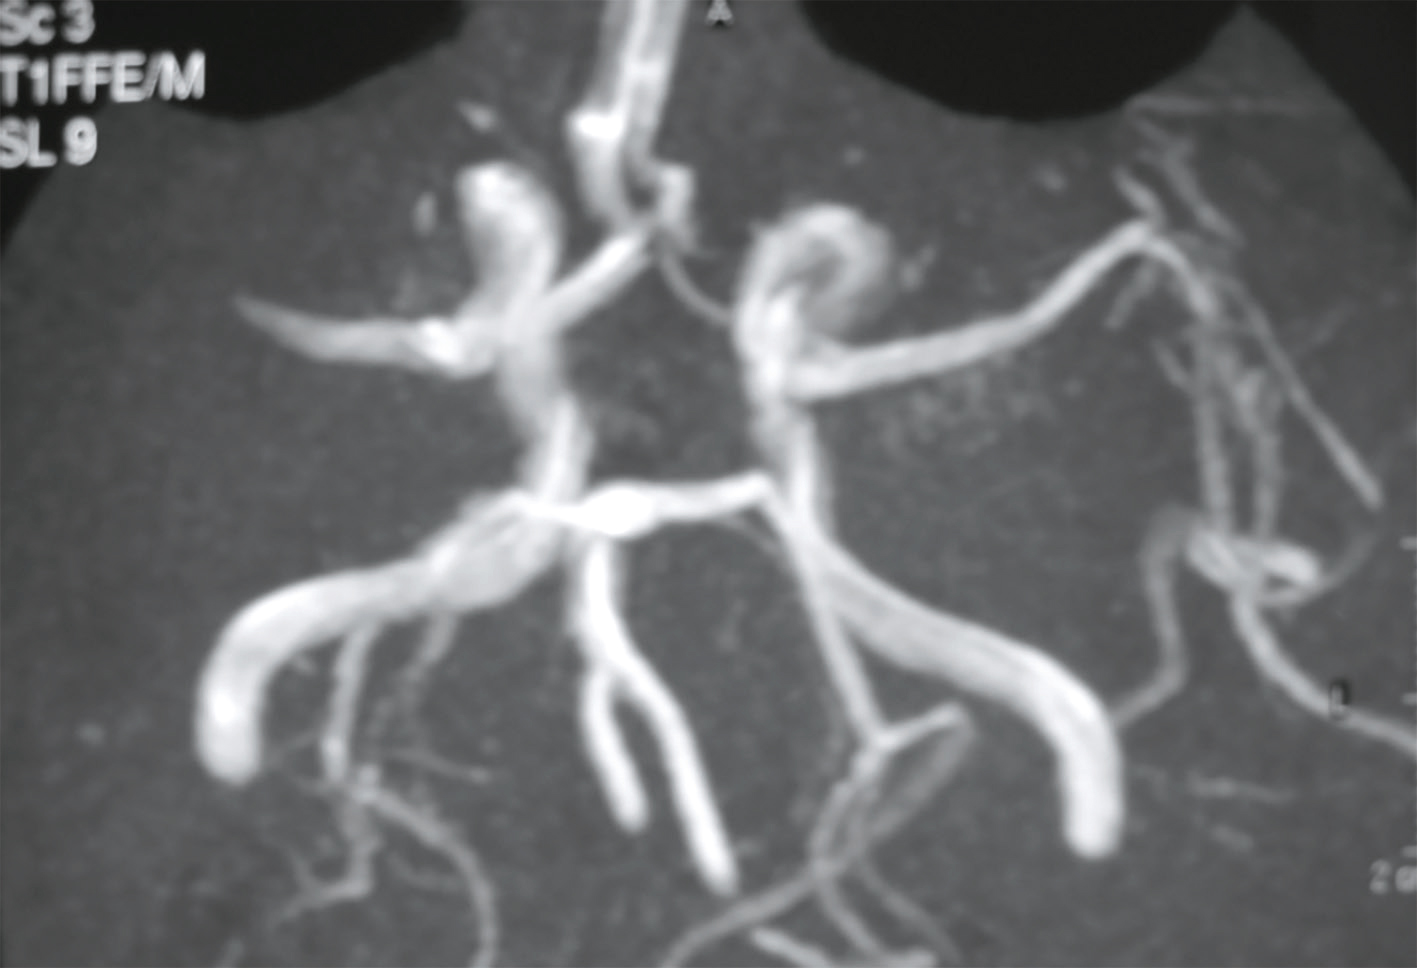

Devant cette atteinte du nerf III avec douleurs associées, vous souhaitez éliminer la présence d’un anévrisme carotidien, raison pour laquelle vous décidez de réaliser une IRM cérébrale avec ARM cervicale. Il n’y a pas d’anévrisme mais d’autres images attirent votre attention. Quelles sont les coupes et séquences utilisées pour ces deux images (fig. 31.12 et 31.13) ?

L'image montre une coupe transversale d'un cerveau humain obtenue par imagerie par résonance magnétique (IRM). Cette image est en niveaux de gris et présente des structures cérébrales distinctes. On peut observer les hémisphères cérébraux, séparés par la fissure interhémisphérique. Les zones plus claires sur l'image représentent des anomalies ou des lésions, qui peuvent être dues à diverses conditions médicales telles que la sclérose en plaques, les tumeurs, ou les accidents vasculaires cérébraux. Les zones sombres au centre de l'image correspondent aux ventricules cérébraux, qui contiennent le liquide céphalorachidien. Cette image est intéressante car elle permet aux professionnels de la santé de diagnostiquer et de surveiller les maladies neurologiques en visualisant les structures internes du cerveau et en identifiant les anomalies. Les détails observables, comme la localisation et la taille des lésions, sont cruciaux pour une évaluation approfondie. Ce type d'imagerie aide à comprendre l'étendue des dommages et à planifier des traitements appropriés. En analysant ces images, les médecins peuvent mieux comprendre la santé cérébrale et prendre des décisions éclairées concernant les soins à apporter au patient.

L'image montre une coupe transversale d'un cerveau humain obtenue par imagerie par résonance magnétique (IRM). Cette image en niveaux de gris présente les structures internes du cerveau, y compris les circonvolutions et les sillons. Les variations de teintes indiquent différentes densités de tissus et de liquides. Les zones plus claires peuvent correspondre à des anomalies ou des lésions, telles que des tumeurs, des plaques ou des signes de maladies neurologiques. Les zones sombres au centre de l'image représentent les ventricules cérébraux, remplis de liquide céphalorachidien. Cette image est utilisée pour diagnostiquer et surveiller diverses pathologies cérébrales, fournissant des informations cruciales pour les professionnels de la santé. L'IRM est une technique non invasive qui permet de visualiser avec précision les détails anatomiques du cerveau sans utiliser de rayonnement ionisant. Grâce à cette image, les médecins peuvent identifier des anomalies, évaluer leur étendue et planifier les traitements nécessaires pour les patients atteints de troubles neurologiques. Les coupes transversales du cerveau montrent également les principales régions cérébrales, permettant une meilleure compréhension de la structure et des fonctions du cerveau humain.

-

- A coupes axiales en séquence T2 injectées

- B coupes axiales en séquence T1 non injectées

- C coupes sagittales en séquence T2/FLAIR

- D coupes axiales en séquence T2/FLAIR

- E coupes axiales en séquence 3D TOF

Les lésions multiples visualisées sur cette IRM cérébrale (une ou plusieurs propositions exactes) :

- A concernent les territoires périventriculaires

- B sont en hyposignal T2/FLAIR

- C ne sont pas responsables d’un effet de masse

- D sont localisées dans la substance grise

- E sont localisées dans la substance blanche